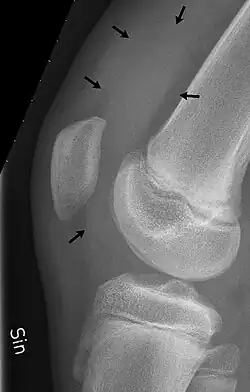

| Traumatic effusion of the right knee, with swelling lateral to the kneecap marked by an arrow | |

X-Ray

An X-ray may be recommended by your provider as a way to obtain a 2-dimensional image to visualize the joint in question. In the presence of trauma an X-ray can be especially useful to verify that there is no break, dislocation, or deformity. In an atraumatic knee, an X-Ray can be used to identify or rule out other causes of a knee infusion including some inflammatory or age-related causes.